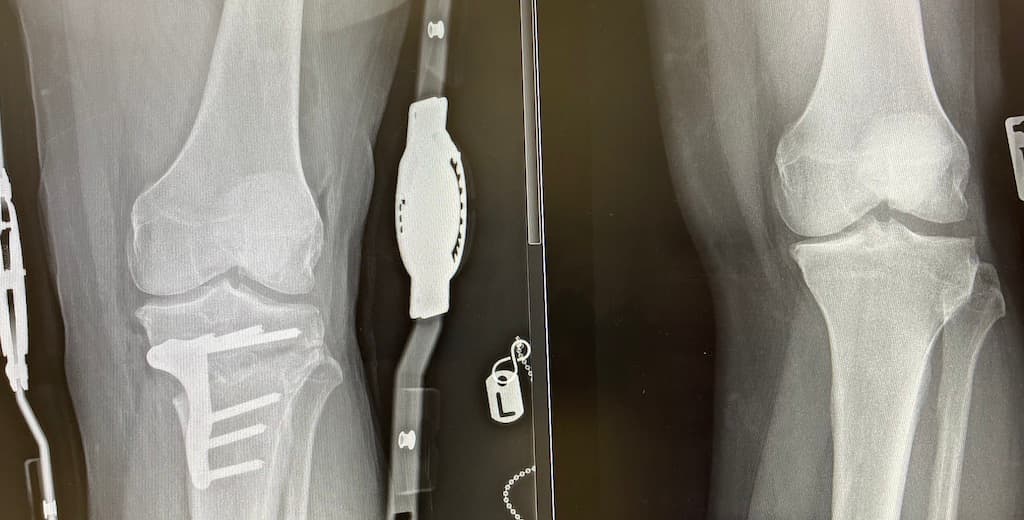

Cartilage injuries pose significant challenges due to poor natural healing, with traditional treatments like debridement and microfracture often yielding limited long-term success. ChondroFiller, a novel biocompatible collagen matrix, offers a minimally invasive alternative that supports natural cartilage regeneration. Studies demonstrate its effective integration and maturation of repaired tissue, with applications extending beyond the knee to the hip joint. Compared to hyaluronic acid injections, which provide symptomatic relief without promoting tissue growth, ChondroFiller may offer more durable repair for suitable cases. Expert consultation is crucial to tailor treatments based on individual patient needs and damage extent. Emerging clinical evidence positions ChondroFiller as a promising advancement in cartilage repair, potentially improving recovery times and outcomes.